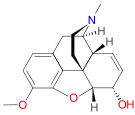

Codeine-dionine family

Structures

| Codeine-dionine family | ||||

|---|---|---|---|---|

6-Monoacetylcodeine 6-Monoacetylcodeine |

Benzylmorphine Benzylmorphine |

Codeine methylbromide Codeine methylbromide |

Desocodeine Desocodeine |

Dimethylmorphine Dimethylmorphine(6-O-Methylcodeine) |

Ethyldihydromorphine Ethyldihydromorphine |

Methyldihydromorphine Methyldihydromorphine(dihydroheterocodeine) |

Ethylmorphine Ethylmorphine |

Heterocodeine Heterocodeine |

Isocodeine Isocodeine |

Pholcodine Pholcodine |

Myrophine Myrophine |

Transisocodeine Transisocodeine | ||